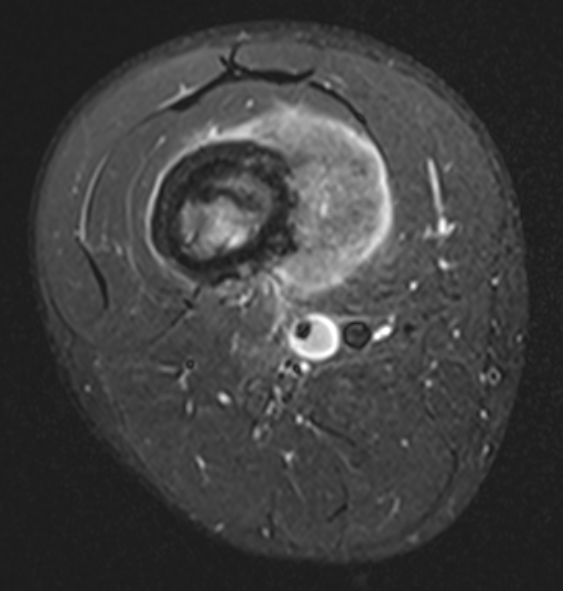

MRI

Evaluate

i) Soft tissue component

ii) Involvement of neurovascular bundle

iii) Marrow extent of tumour

- helpful in determining appropriate resection level

- satellite lesions - metastasis within reactive zone

iv) Identify skip lesions

- metastasis outside reactive zone

- sagittal and coronal images of the entire bone

v) Joint involvement